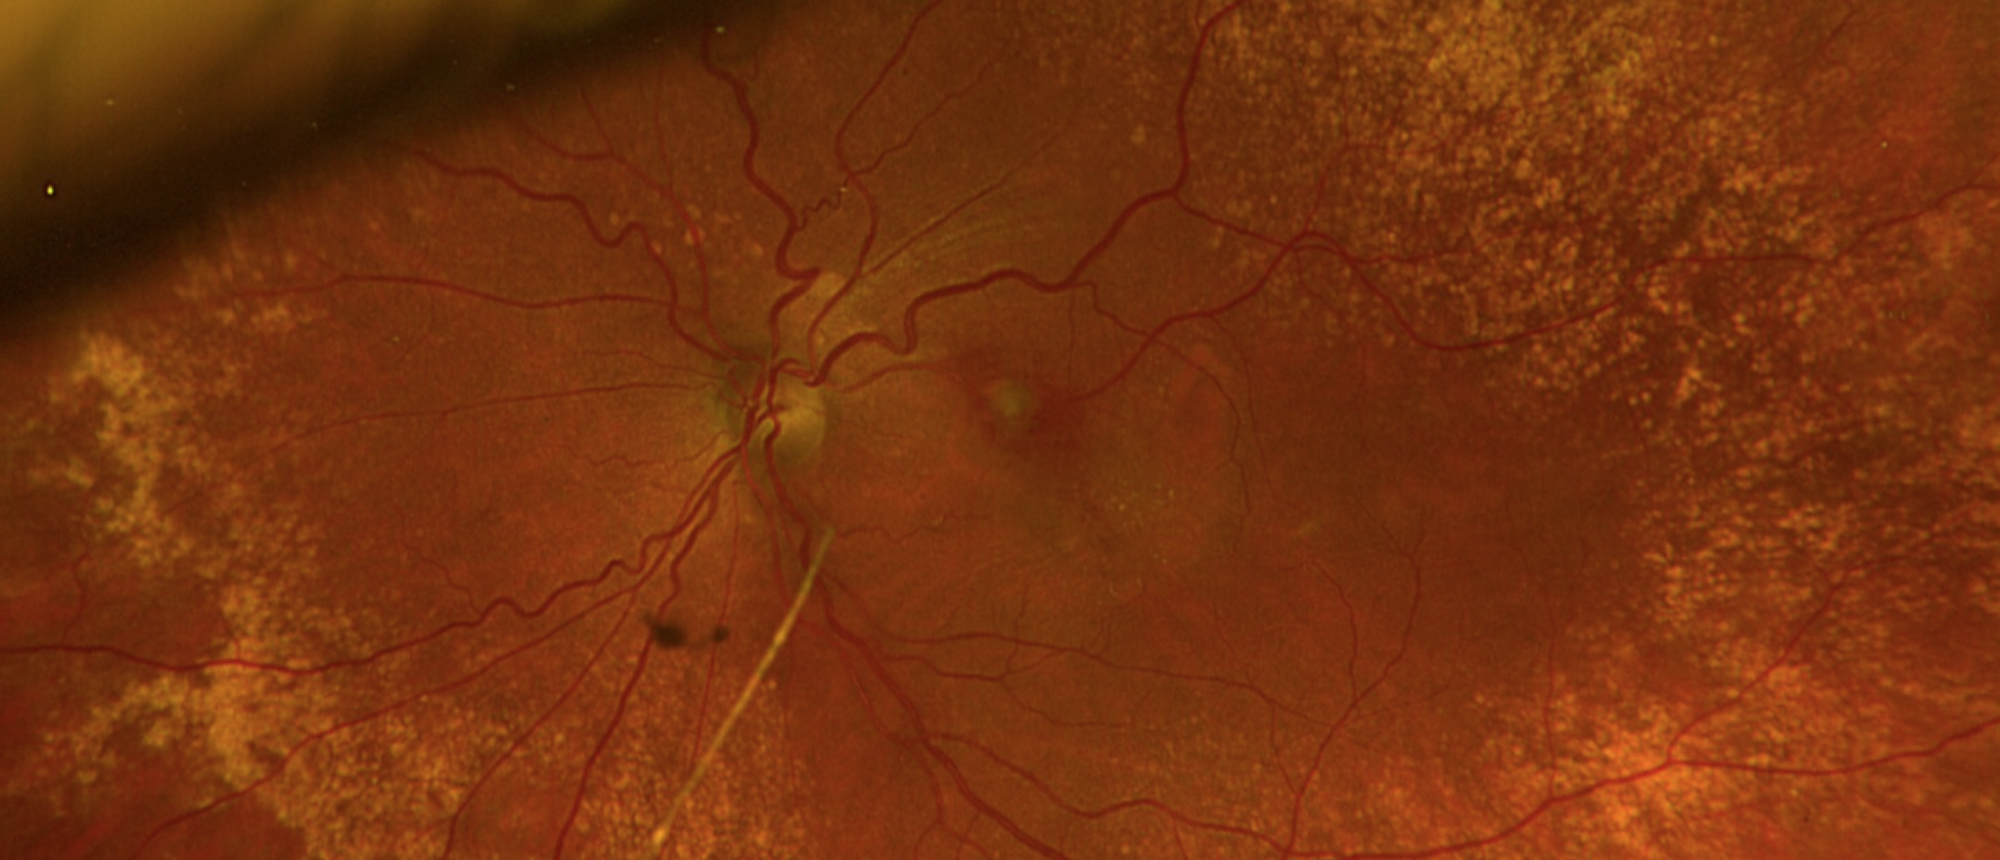

Recurrent Idiopathic Neuroretinitis A patient presented with 1 day of decreased vision in 2016. Exam disclosed OS>>OD optic nerve edema with visual field defects without other findings. The patient was treated with steroids without much improvement and lost to follow up. The patient then over…